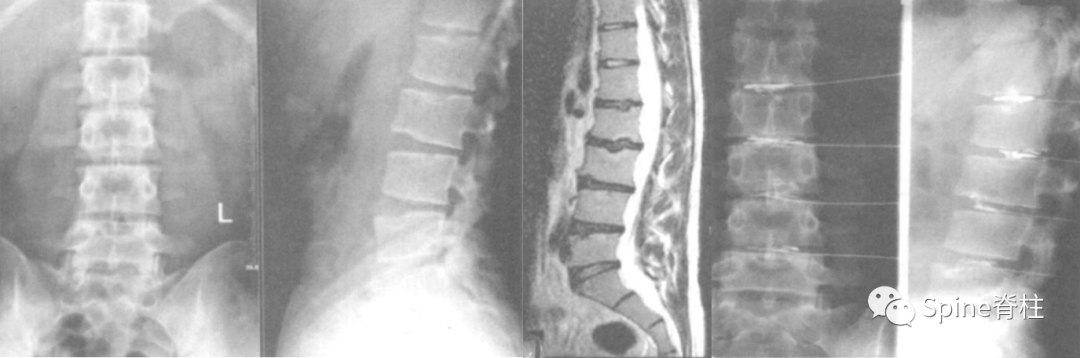

文献中诊断的腰型休门氏病典型图片:

腰型休门氏病椎体终板不规则,T11-L4椎体中央Schmorl节,L2、L5椎体前缘Schmorl节,L2-L3椎间盘损伤(PMID: 24468666)。

腰型休门氏病。矢状位示腰1-2椎体轻微楔形变,冠状位示腰2椎体下缘及腰3椎体上下缘终板中央区略显凹陷;腰1椎体下缘,腰2-3椎体上下缘及腰 4 椎体上缘许莫氏结节;胸12-腰1椎体相邻缘终板中央偏后区不规则、略显内凹伴硬化。MRI上腰1-3椎体上缘许莫氏结节 (doi:10.3969/j.issn.1005-7234.2016.03.003)。